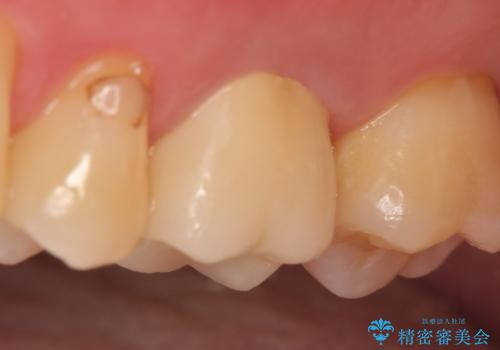

検査の結果歯の神経が死んでいたため根管治療を施し、症状が治まったのを確認後オールセラミッククラウンによる補綴を行いました。

今回用いたオールセラミッククラウンはジルコニアフレームという白い素材の上にセラミックを盛っているため、審美性が非常に高いのが特徴です。

また、ジルコニアは人工ダイヤモンドの材料にも使われているほど高い強度を持っており、そのためオールセラミッククラウンは審美性だけでなく、奥歯やブリッジの補綴も可能とするクラウンです。